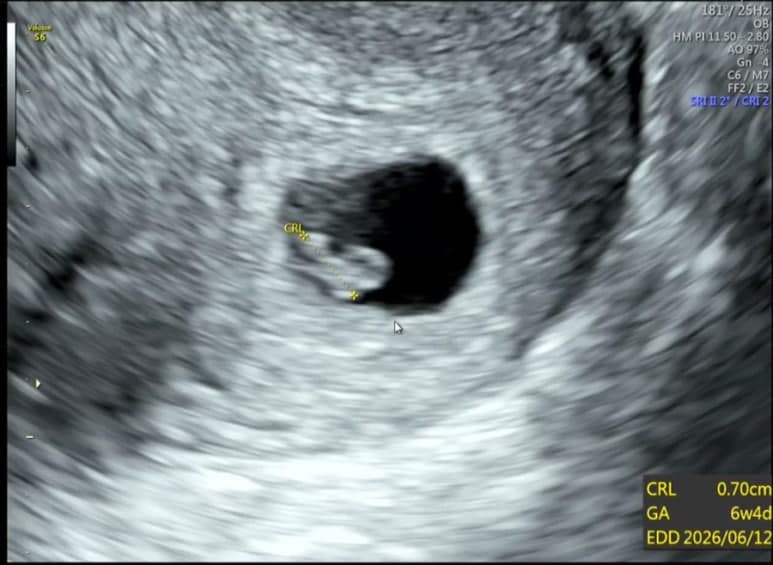

초음파 화면에 작은 점 하나가 보이고.

그 다음 순간,

두근, 두근, 두근.

심장 소리가 들렸다. 0.7cm 밖에 안되는 한 존재가 나에게로 왔다.

그 작은 심장이 이렇게나 힘차게 뛰고 있었다니.

내 안에 심장이 두개가 있다!!🤍